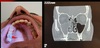

37

Dx

Sinusitis maxiloetmoidal

38